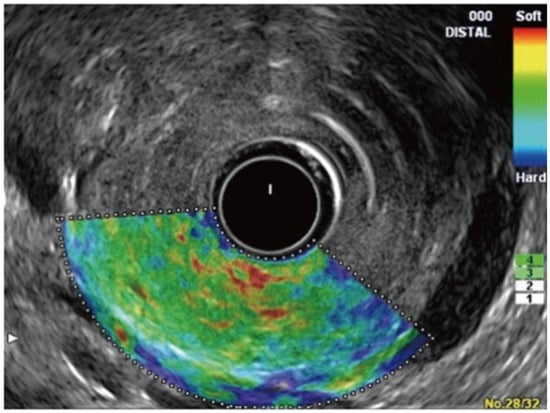

5. Real-Time Elastography–Endoscopic Ultrasound

- Strain Elastography (Qualitative Elastography): It estimates the stiffness of the tissue by measuring the degree of strain [29,52]. The results are interpreted with the help of a colored scale, wherein red-green areas indicate softer tissues and blue areas indicate stiffer tissues [29,52]. The main limitations of qualitative elastography are that it lacks reproducibility as the interpretation of the colors is highly operator-dependent, and it provides limited information when comparing results for different patients and lesions [54,55].

- Shear-Wave Elastography (Quantitative Elastography): It measures tissue stiffness by measuring the propagation of the shear waves, which is the emission of focused waves from the probe to the target lesion, also known as acoustic radiation force impulse [29]. Another method of shear-wave elastography is the semi-quantitative analysis, which allows for the measurement of tissue stiffness by calculating the strain ratio (ratio of stiffness of area of interest on the target tissue and smaller region of interest of a reference tissue) and strain histogram technique where an average hue histogram represents the colors and thereby the stiffness of the tissue [56]. It is important to note that only strain elastography is available with EUS for the evaluation and characterization of pancreatic lesions [29].